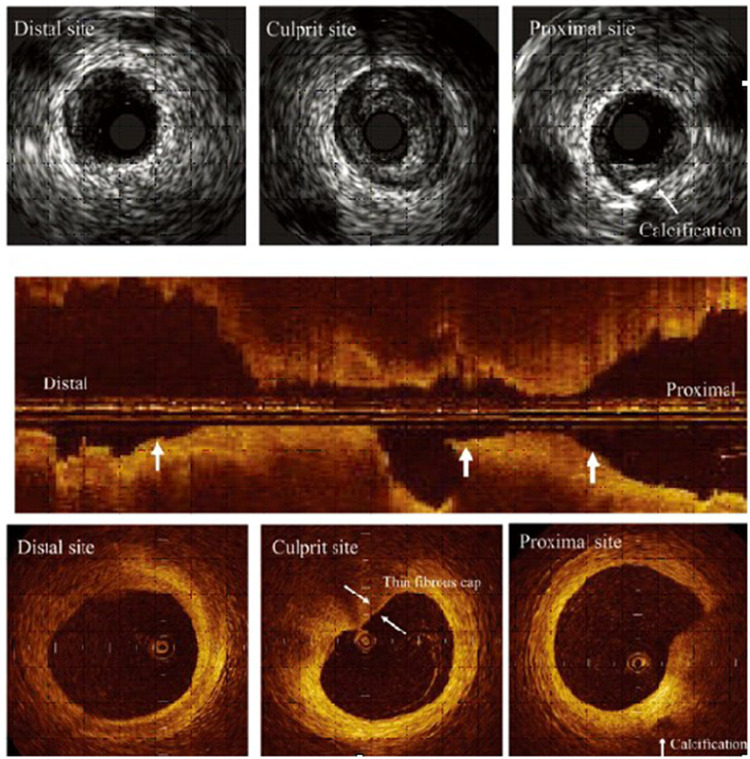

Abstract Image